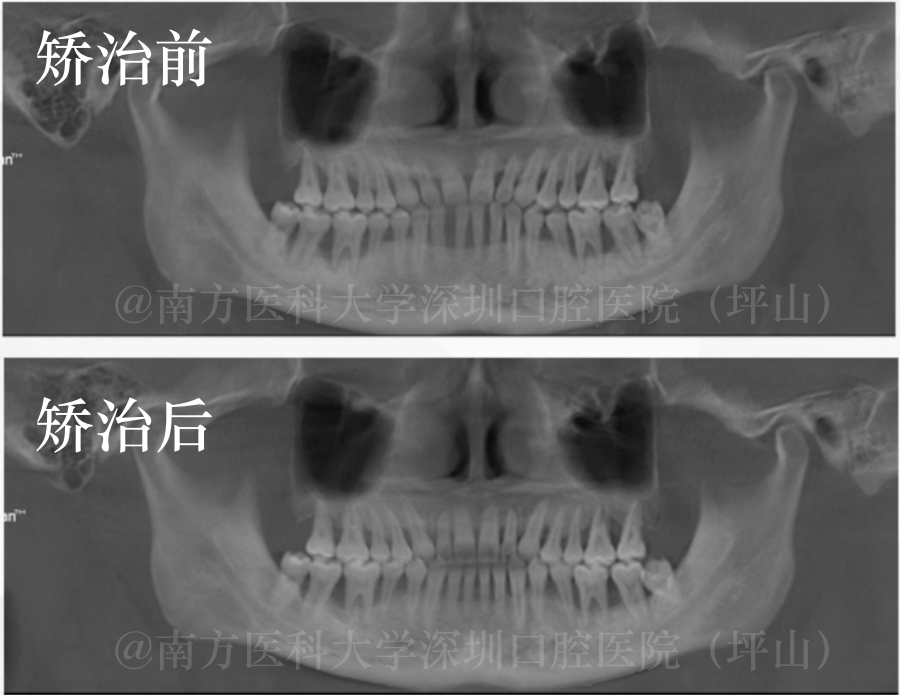

矫治过程回顾

矫治前

矫治后

整个矫正时间历时1年4个月,通过医生及患者的积极配合,最终达到了患者满意的效果。